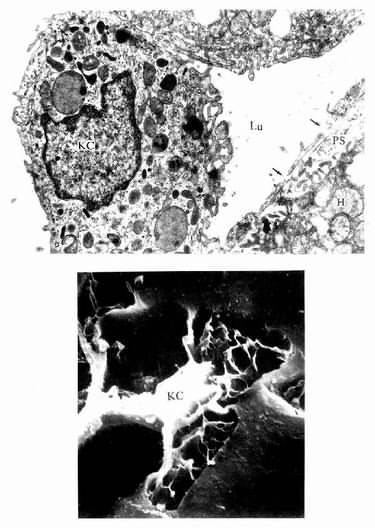

肝巨噬细胞:又称枯否细胞(Kupffer cell),是定居在肝内的巨噬细胞。细胞形态不规则,有许多板状或丝状伪足,细胞表面有许多皱褶和微绒毛,并有较厚的糖衣。细胞常以其伪足附于内皮细胞上或穿过内皮细胞窗孔或细胞间隙伸入窦周隙内(图13-16)。胞质内溶酶体甚多,并常见吞噬体和残余体。肝巨噬细胞来自血液单核细胞,是体内固定型巨噬细胞中最大的细胞群体。肝巨噬细胞具有变形运动和活跃的吞饮与吞噬能力,构成机体一道重要防线,尤其在吞噬清除从胃肠进入门静脉的细菌、病毒和异物方面起关键作用。肝巨噬细胞还可监视、抑制和杀伤体内的肿瘤细胞,尤其是肝癌细胞,并能吞噬和清除衰老、破碎的红细胞和血小板等。此外,肝巨噬细胞还有处理和传递抗原、诱导T细胞增殖及参与调节机体免疫应答等作用。

图13-16 肝巨噬细胞(KC)电镜像

上图 大鼠肝 ×24000(上海医科大学电镜室供图)

Lu血窦腔,H肝细胞,PS窦周隙,↑内皮细胞孔

下图足月胎儿冷冻割断扫描电镜像

(河北医学院吴淑兰教授供图)